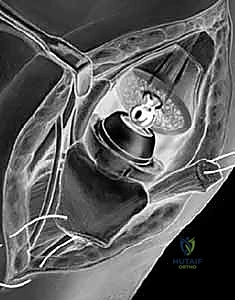

1. استئصال العظم المربعي مع إعادة بناء الأربطة (Trapeziectomy with LRTI)

تُعد هذه العملية "المعيار الذهبي" (Gold Standard) والأكثر شيوعاً ونجاحاً عالمياً لعلاج هذه الحالة.

• آلية العملية: يقوم الجراح بإزالة "العظم المربعي" (Trapezium) بالكامل، وهو العظم الذي يسبب الاحتكاك المؤلم. بمجرد إزالته، يختفي الألم تماماً لأنه لم يعد هناك عظم يحتك بعظم.

• **إعادة بناء الأربطة (LRTI):